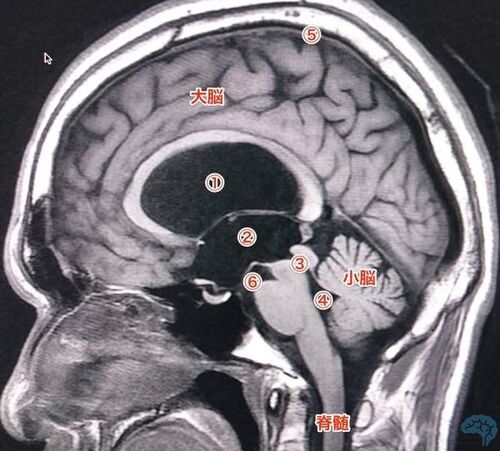

水頭症を分類してみよう(総論的な話)

水頭症とは、簡単にいうと 頭に水がたまって悪さをする病気 であるが、もう少し詳しく説明してみる。